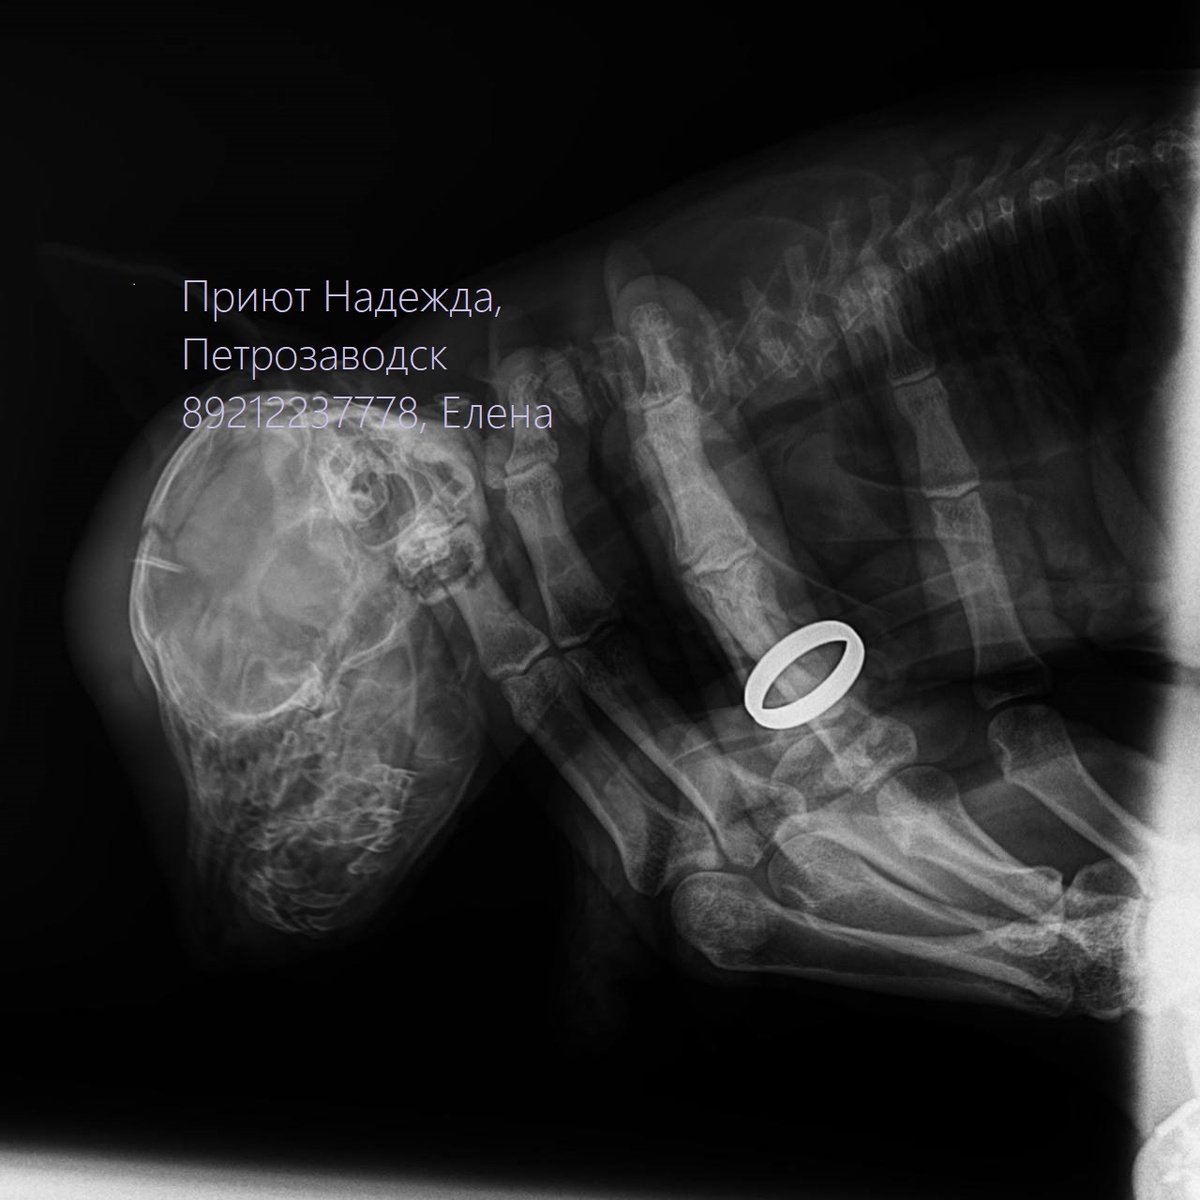

Приют Надежда, г. Петрозаводск Маленького Ежика принесли в клинику на усыпление. Типичная история: травма, лечить нехоца, нет денег, желания - усыпить дешевле и никаких усилий не нужно. По рентгену в петрозаводской ветклинике врачи увидели трещину в черепе и гематому. Есть ли осколки или нет можно определить только по результатам МРТ, которую можно сделать только в Санкт-Петербурге. Отправила снимки хирургам в клинику Сотникова в Санкт-Петербурге и упала от отчаяния: ПО СНИМКАМ НЕ ТРЕЩИНА, ПО СНИМКАМ- ПЕРЕЛОМ ЧЕРЕПА И ГЕМАТОМА!!! Вопрос нужно МРТ или нет отпал сам собой. Нас отправляют на МРТ и если есть осколки в черепе - ОПЕРАЦИЯ! Малыша Ёжика нужно спасать. Сейчас Ежик в кислородной камере, борется за свою жизнь. ПРОШУ СРОЧНОЙ ПОМОЩИ НА СПБ!!! Боженьки, мне страшно до невозможного. Понимаю, НЕ ВЫТАЩИТЬ МАЛЯВКУ БЕЗ ПОМОЩИ ХИРУРГА- НЕВРОЛОГА. Помогите выжить малышу! Он еще толком и жизни не видел, не успел узнать что такое быть любимым. У меня нет денег совсем, долги за бездо

По рентгену в петрозаводской ветклинике врачи увидели трещину в черепе и гематому.

Есть ли осколки или нет можно определить только по результатам МРТ, которую можно сделать только в Санкт-Петербурге.

Отправила снимки хирургам в клинику Сотникова в Санкт-Петербурге и упала от отчаяния: ПО СНИМКАМ НЕ ТРЕЩИНА, ПО СНИМКАМ- ПЕРЕЛОМ ЧЕРЕПА И ГЕМАТОМА!!!

Нас отправляют на МРТ и если есть осколки в черепе - ОПЕРАЦИЯ!